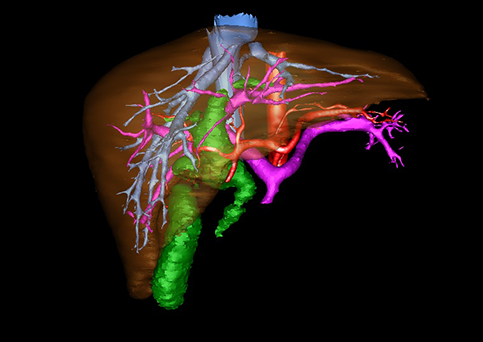

10、三维重建虚拟肝脏、胆道显像技术

三维虚拟肝脏技术是在二维影像学资料如CT等图像的基础上,通过三维重组软件和工具,比如青岛大学附属医院与海信医疗集团联合自主研发的海信计算机辅助手术系统(Hisense Computer Assisted Surgery,Hisense CAS),目前已投入临床并指导实际应用,利用该类系统对二维影像学的数据资料进行三维立体分析,重组形成立体的、有空间结构的、虚拟的肝脏三维图像。这项技术较传统的二维平面成像技术,有着明显的优势,3D虚拟肝脏技术可以构造出一个虚拟的、可视化的肝脏模型。通过对这种模型的观察,可以很容易地分辨出肝脏器官的组织结构、解剖特点,直观研究肝外胆总管的形态差异,明确肝内胆管的形态、走形、是否合并扩张、狭窄及结石,胰胆管合流的形态及共同通道内是否有狭窄、扩张和结石等病变情况,预先规划处理可能合并存在的肝内胆管扩张、狭窄或其他复杂胆道畸形,清晰地显示肝内脉管系统,包括门静脉、肝动脉及肝静脉的走行、分支,并可多角度、全方位观察病变胆道与其周围重要血管尤其是伴行的门静脉之间的解剖关系,大大提高了外科医师在术前对肝脏内部各管道结构及其变异判断的精确性和可靠性,精准地对病变进行判断和评估,还可根据患者自身的病变特点,制定出合理、个体化的手术方案,最大限度地降低术中和术后并发症发生率,并术中导航实时指导手术,提高手术的精准性和成功率。

图10:先天性胆管扩张症囊肿型三维重建虚拟肝脏、胆道显像

a 图为术前二维CT扫描图像,箭头所示为肝内胆管扩张;b 图为CT经多平面重组技术(MPR)图像后处理所得的重建图像,可显示胆总管明显扩张合并肝内胆管扩张;c 图为MRCP显示胆总管呈囊柱状扩张,直径>1 0 cm,伴肝内胆管扩张;d 图示Hisense CAS三维重建清晰显示肝脏、胆道系统及其与门静脉、肝动脉、肝静脉等之间的空间解剖关系;e 图示Hisense CAS可从任意角度以不同脏器组合显示,明确胆道系统与其伴行的门静脉系统的空间解剖关系;f 图示胆道系统立体形态及与肝脏整体的空间关系,箭头处显示肝内胆管狭窄部位发生于左右肝管汇入肝总管处。术前规划需行肝内胆管扩大成形术。

图11:先天性胆管扩张症梭状型三维重建虚拟肝脏、胆道显像

a 图为术前二维CT扫描图像,箭头指示肝内胆管扩张;b 图为CT经多平面重组技术(MPR)所得的重建图像,可粗略地判断病变胆管的位置;c 图示术前Hisense CAS三维重建清晰显示胆管的病理形态及其与肝内三套血管系统的解剖关系;d 图示胆道系统与其伴行的门静脉系统的空间解剖关系;e 图为胆道系统立体形态,箭头处指示迷走胆管,源自肝脏直接汇入胆总管。术前规划先将迷走胆管与肝总管吻合成形,再行肝总管空肠Roux-en-Y吻合术。

图12:先天性胆管扩张症梭状型合并左右肝管分别汇入胆总管囊肿三维重建虚拟肝脏、胆道显像

a 图为术前二维CT图像;b 图为CT经多平面重组技术(MPR)所得的三维重建图像,可粗略地判断病变胆管的位置;c 图为MRCP显示胆总管梭状扩张;d 图为术前Hisense CAS三维重建显示胆管的分布走形及其与肝内三套血管系统的解剖关系;e 图为胆道系统立体形态及与肝脏整体的空间关系,箭头处显示对于左右肝管分别汇入胆总管囊肿中,整个肝总管也明显扩张而成为囊肿的一部分。术前规划为先将囊肿完全切除,左右肝管合并成形后再与空肠吻合。